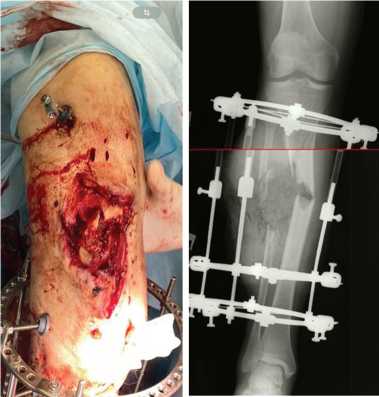

После стабилизации состояния и заживления ран на левой голени (рис. 1) через 72 дня после ранения провели операцию: внеочаговый чрескостный компрессионно-дистракционный остеосинтез (ВЧКДО) по Илизарову левой голени, остеотомия дистального отломка левой большеберцовой кости. Дефект большеберцовой кости — 15 см. На 79-е сутки после ранения начали перемещение фрагмента с целью формирования регенерата и замещения дефекта. На 164-е сутки после ранения (85 суток после остеотомии) для коррекции положения и направления перемещения фрагмента выполнили перемонтаж аппарата Илизарова на левой голени. Продолжили перемещение фрагмента дистального отломка большеберцовой кости (рис. 2).

Рис. 1. Фото и рентгенограмма левой голени перед реконструктивной операцией

Рис. 2. Фото и рентгенограмма левой голени в процессе транспорта кости